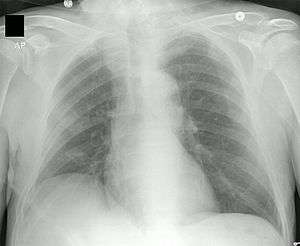

Chest X-ray showing tip of PICC line in the superior vena cava

A peripherally inserted central catheter (PICC or PIC line), less commonly called a percutaneous indwelling central catheter, is a form of intravenous access that can be used for a prolonged period of time (e.g., for long chemotherapy regimens, extended antibiotic therapy, or total parenteral nutrition) or for administration of substances that should not be done peripherally (e.g., antihypotensive agents aka pressors). It is a catheter that enters the body through the skin (percutaneously) at a peripheral site, extends to the superior vena cava (a central venous trunk), and stays in place (dwells within the veins) for days or weeks.

A PICC is inserted in a peripheral vein in the arm, such as the cephalic vein, basilic vein or brachial vein, and then advanced proximally toward the heart through increasingly larger veins, until the tip rests in the distal superior vena cava or cavoatrial junction.